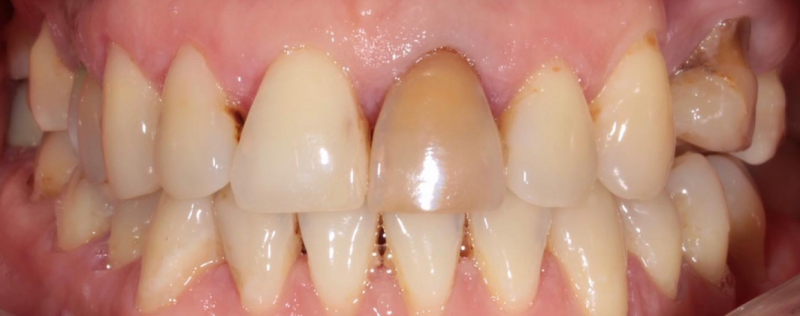

На странице представлено портфолио стоматологий Санкт-Петербурга с работами до и после профессиональной чистки зубов. В нашем портфолио собраны разные клинические случаи: от удаления незначительного налета до снятия массивного поддесневого камня. Здесь вы можете увидеть, как возвращается естественный цвет и внешний вид зубов после процедуры. Изучите результаты до и после чистки зубов, чтобы увидеть реальный эффект и выбрать клинику в Санкт-Петербурге, где профессиональная гигиена поможет вернуть зубам здоровый вид.